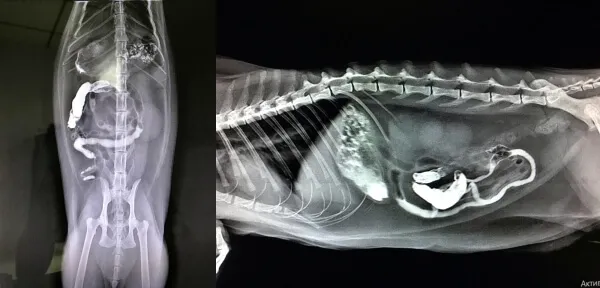

Активные собаки, особенно молодые и любопытные, часто подбирают и проглатывают посторонние предметы. Это может быть игрушка, кость, палка, фрагмент пищевой упаковки или даже шип растения. Иногда инородное тело проходит естественным путём, но в ряде случаев оно застревает — в пищеводе, желудке, кишечнике, носовых ходах или ушах. Последствия могут быть серьёзными: от воспаления до перфорации органов. Диагностика таких случаев — задача непростая, особенно когда предмет не виден на обычном рентгене. На помощь приходит компьютерная томография для собак в Москве (КТ), которая позволяет точно локализовать даже те объекты, которые «невидимы» для стандартной рентгенографии.

Компьютерная томография даёт трёхмерное изображение тела срез за срезом, что позволяет:

- Видеть объекты с низкой плотностью (например, деревянную палочку).

- Точно определить местоположение — в пищеводе, желудке, кишечнике, носовой полости.

- Оценить степень повреждения окружающих тканей: отёк, перфорацию, абсцесс.

- Получить данные в нескольких проекциях без перемещения животного.

- Лабрадор, 2 года: постоянная рвота, но рентген чист. КТ выявил пластиковую крышку от бутылки, застрявшую в пилорическом отделе желудка. Успешно удалена хирургически.